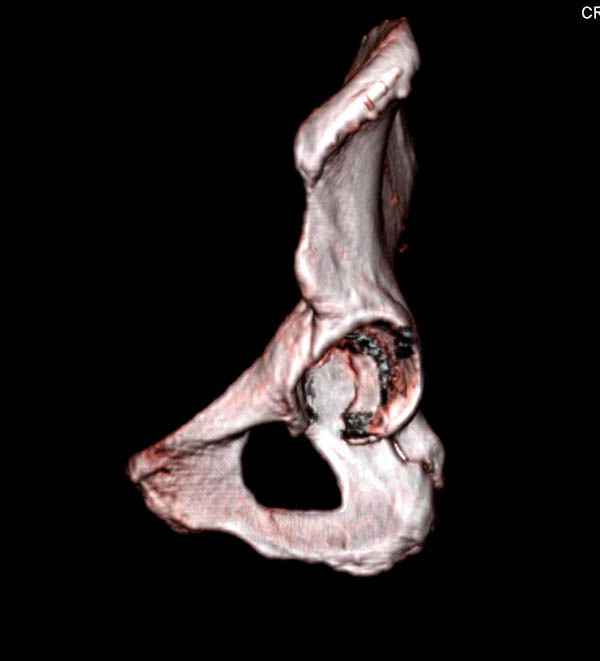

На снимке ацетабулума редко встречающийся очень низкий перелом,

наверное, трудно было репозицию через один доступ? Перелом как бы

замкнулся в квадрилатеральной поврехности.

Вложение не в текстовом формате было извлечено…

Имя     : 12 acetabulum fem neck 3D.jpg

Тип     : image/jpeg

Размер  : 23128 байтов